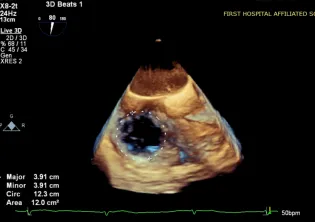

超声评估:1.三尖瓣关闭不全,重度反流(5+);2.反流口位于前隔、中央;3.三尖瓣环扩张(平均瓣环径:43.5mm)。

超声基线

实时3D